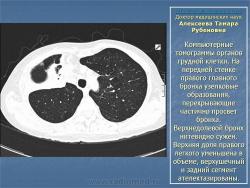

Доктор медицинских наук  Алексеева Тамара Рубеновна

Туберкулез внутригрудных лимфатических узлов.